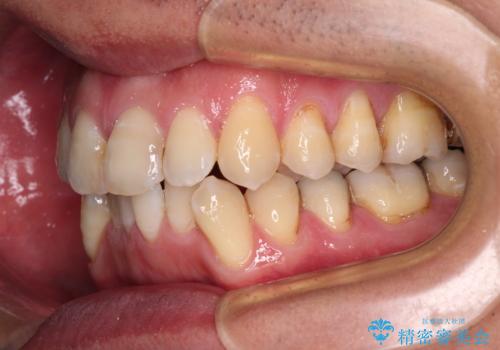

- 前歯のデコボコを気にして来院された患者様です。

下顎前歯のデコボコが特に強く、治療を早く終えることを考えるとワイヤー装置がお勧めですが、ワイヤー装置の異物感は避けたいのでインビザラインを希望されていました。

インビザラインで治療を行うか、ワイヤーで治療を行うかずっと悩んでいらっしゃいましたが、早く終わらせることを優先してワイヤー装置にて治療を行うこととしました。

下顎にワイヤー装置を装着し、暫くしたところでやはりインビザラインにて矯正治療をしたいとのことで、インビザラインに切り替えました。

短い期間でしたがワイヤー装置を使用したことでデコボコが解消されたため、インビザラインの比較的短い期間で矯正治療を行うことができました。